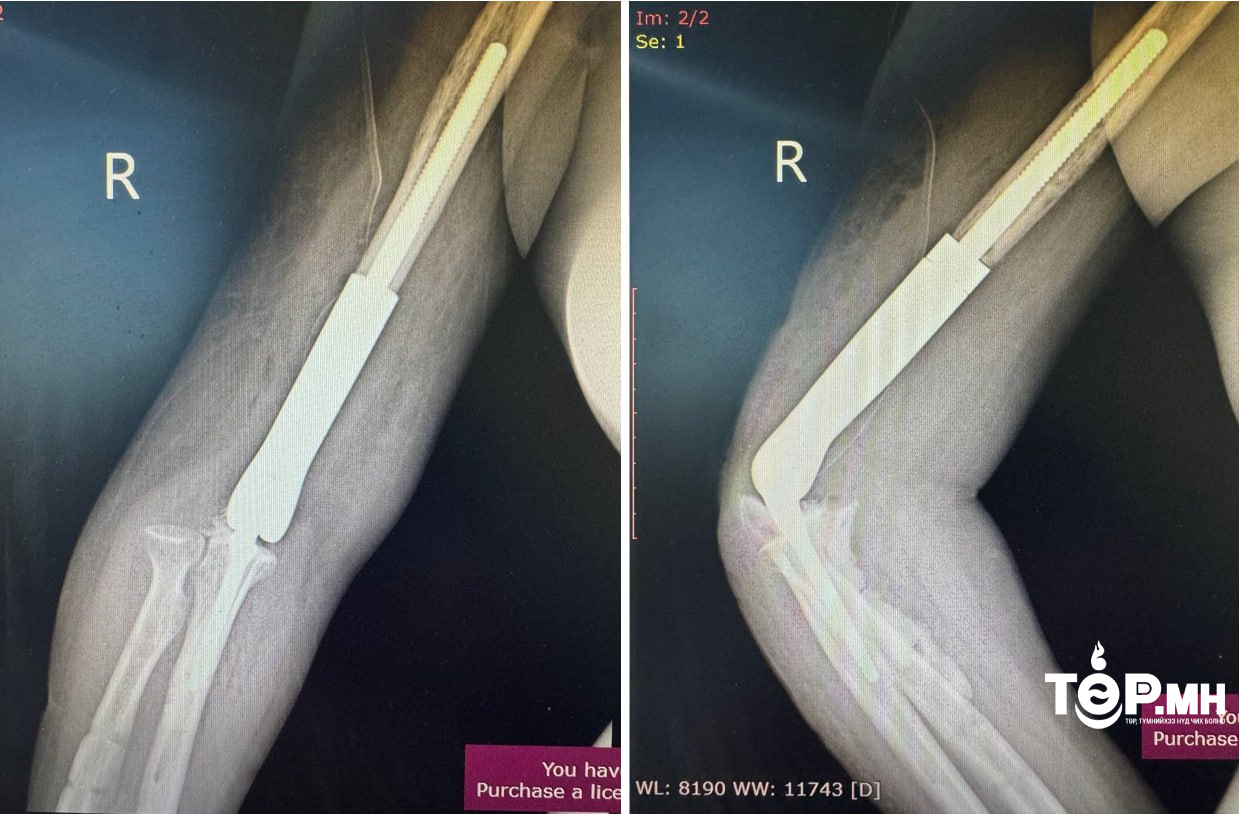

Уг мэс засал нь авто ослын дараах атгаалын чөмөгт ясны доод хэсэг бяцарч, үйрмэг мэт болон хугарч, эргэн сэргэшгүй болж дутмагшил үүссэн (10см орчим) ясыг орлуулах, үеийг орлуулсан, нийлмэл тохойн хиймэл үе бүхий имплантыг суурилуулан гарын хөдөлгөөнийг бүрэн сэргээж, амьдарлын чанарыг сайжруулах мэс засал эмчилгээ юм.

Тус мэс заслын баг бүрэлдэхүүнд ГССҮТ-ийн Гар сарвууны мэс заслын тасгийн эрхлэгч Л.Нанжид болон их эмч Ж.Баярмагнай, Т.Баян-Өлзий, Ц.Санжаасүрэн, мэдээгүйжүүлэгийн эмч Г.Ариунболд, сувилагч Т.Гантулга, Б.Базаррагчаа, Г.Ганцэцэг нар багтсан.

Үйлчлүүлэгчийн биеийн байдал тогтвортой байгаа бөгөөд мэс засал эмчилгээний дараах нөхөн сэргээх эмчилгээнд хамрагдаж байна.